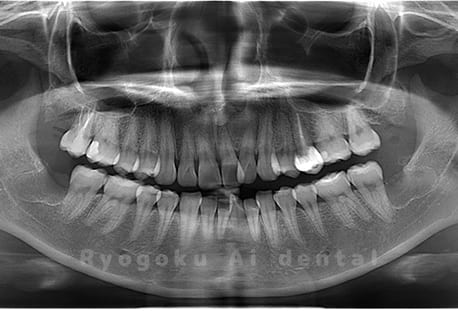

真っ直ぐ生えている親知らず

親知らずが真っ直ぐ生えているタイプです。

このタイプは真っ直ぐ生えていて咬み合わせに問題がなければ、抜歯しないケースもあります。ただし、虫歯になっていたり、痛みがあったり、咬み合わせが悪かったりすると抜歯をおすすめします。